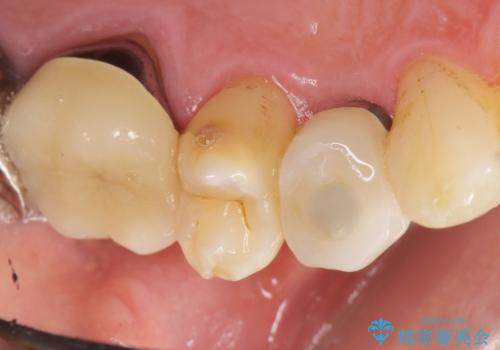

歯科治療や外科手術が苦手な患者様で、治療前はとても怖がっていましたが、インプラント手術後には「思ったよりも大変ではなかった」とおっしゃって下さいました。

元の歯のように咬むことができ、見た目も自然だと喜んで頂けました。

他の部位のインプラント治療もご希望され、現在治療中です。

インプラントの種類:スプライン ツイスト

被せ物の種類:メタルボンドクラウン

固定様式:スクリュー固定